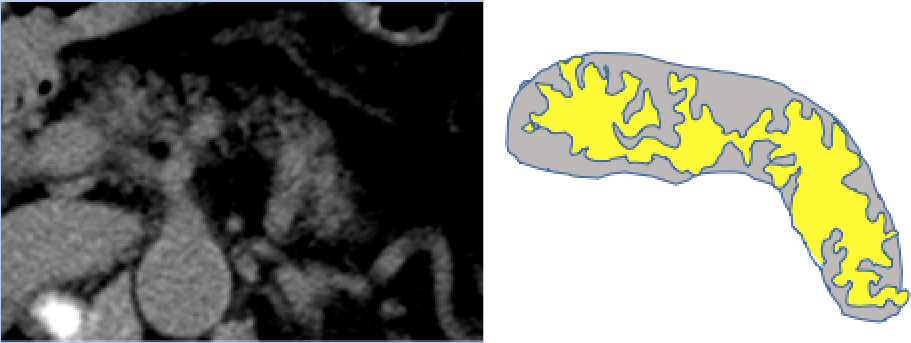

③ 膵脂肪変性(凹み)、膵管拡張

⑤ 脂肪変性

膵頭部(鉤部:こうぶ)脂肪変性

お腹や胸のCTを撮影したことのある人は膵臓に上記のような変化がないか主治医の先生に確認してもらいましょう。CTを何度か撮影したことがある人は比較してもらいましょう。胸のCTにも膵臓は一部うつっていることが多いです。